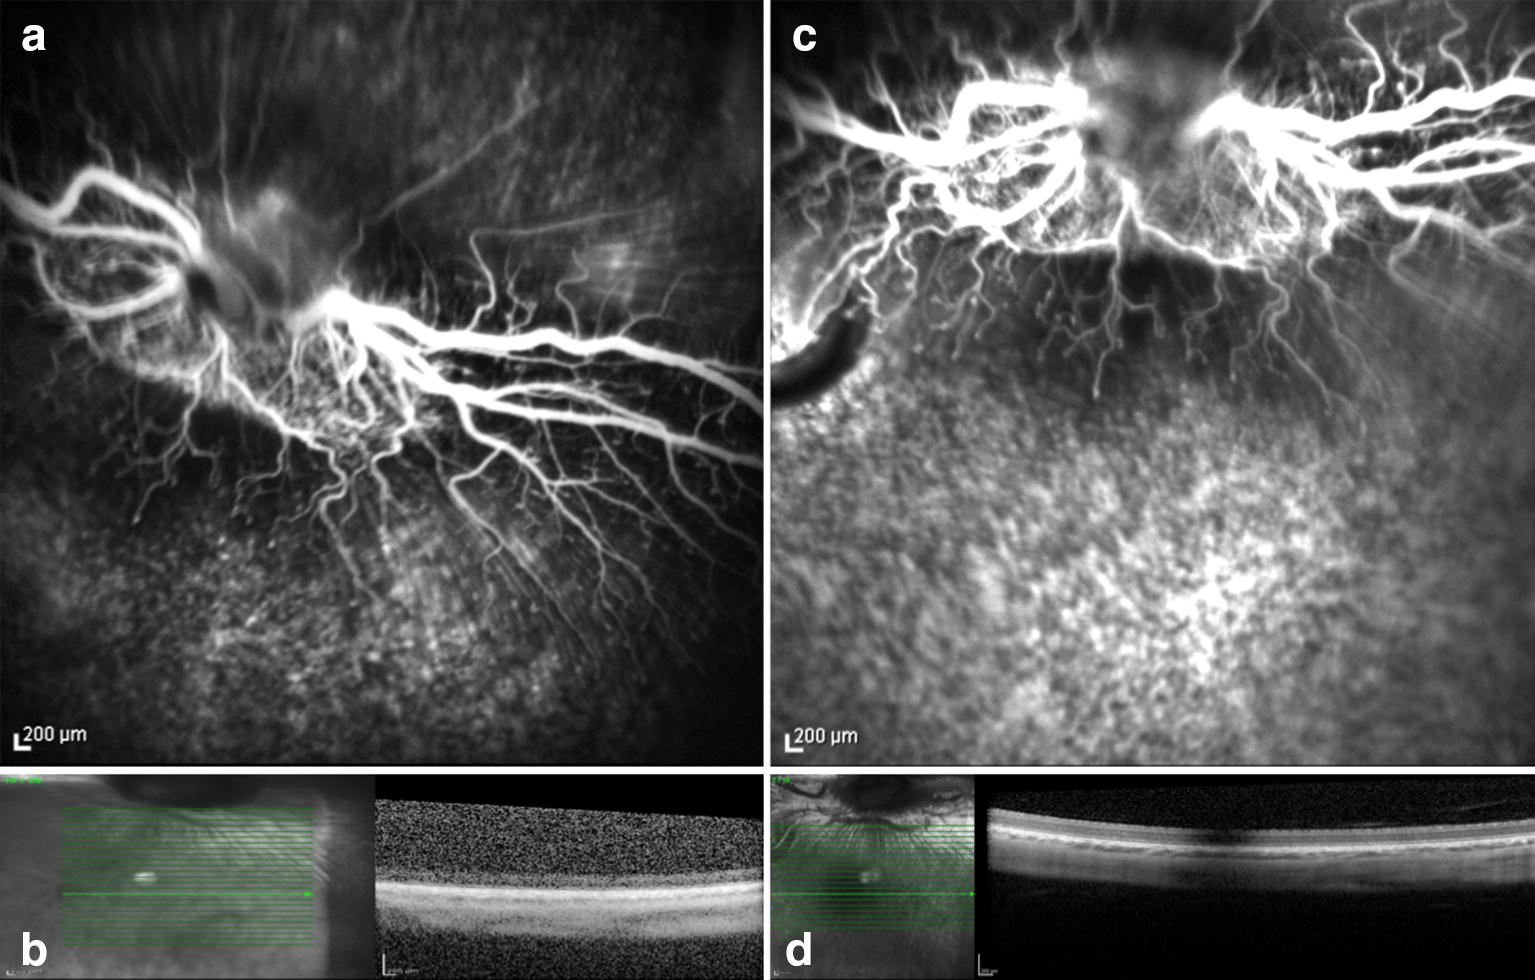

Fig. 7.

Preoperative (a and b) and seven days postoperative (c and d) fluorescein angiography and OCT. Rabbit (no.16) exposed to 435 nm illumination without the administration of lutein. Postoperative hyperfluorescence (c) corresponds to the exposed area and increased reflective of the inner and outer layers of the retina with tissue thinning evidenced by examining OCT (d)

The FA and OCT from the subgroup exposed to the two different wavelengths without systemic administration of lutein (control groups) are presented on Figs. 6 and 7. The ERG from the same group is shown on the Figs. 10 and 11.